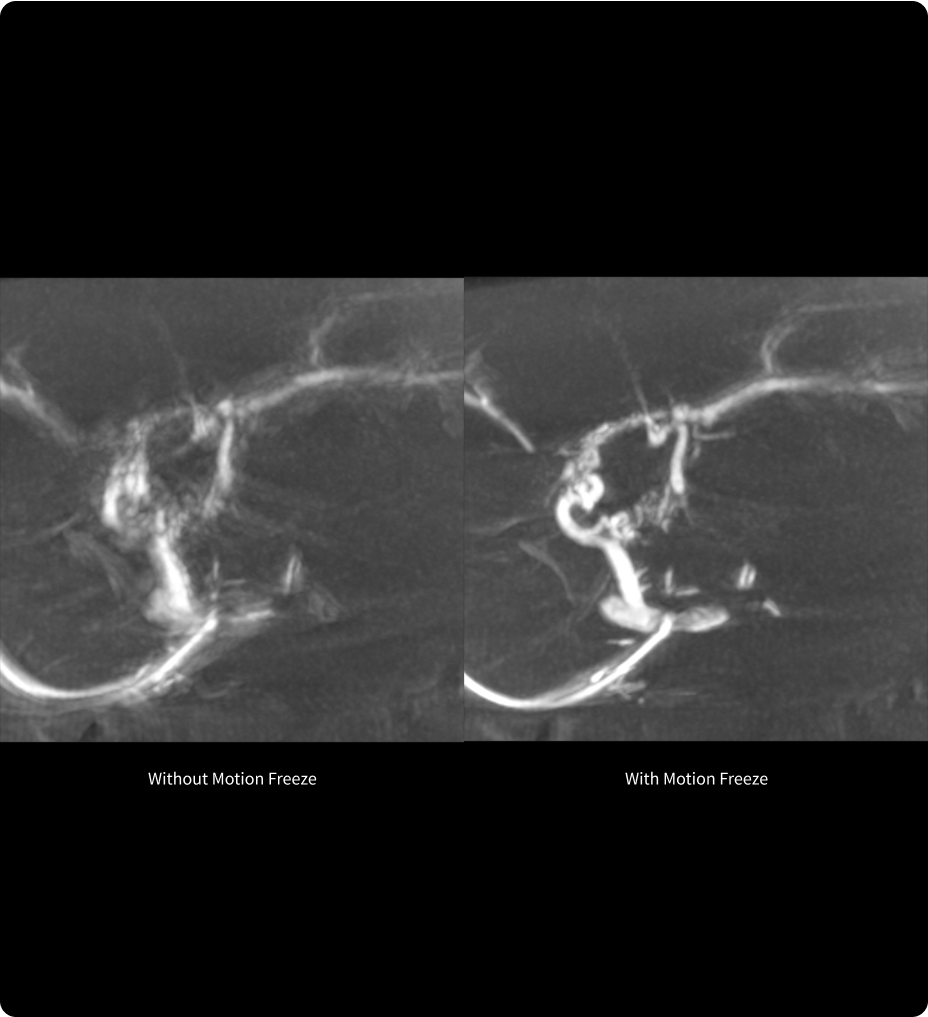

Diagnóstico más fundamentado con mayor inteligencia de imágenes mediante Smart MAR

Smart MAR se ha diseñado para mostrar detalles anatómicos que se ven oscurecidos a causa de los artefactos metálicos, de modo que los profesionales de la salud pueden usar exploraciones de TC, diagnosticar enfermedades y definir objetivos y órganos críticos con mayor confianza.